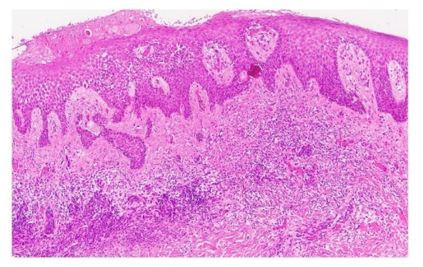

After evaluating the patient, the Meyerson phenomenon was considered, and the lesion was excised for histopathological analysis, confirming the diagnosis (Figure 1C). The patient is currently under clinical follow-up and has not presented any further symptoms to date.

Figure 1 Histopathology revealing mild spongiosis, acanthosis, perivascular lymphocytic infiltrate with scattered eosinophils in the superficial dermis, and preservation of the underlying melanocytic nevus architecture.